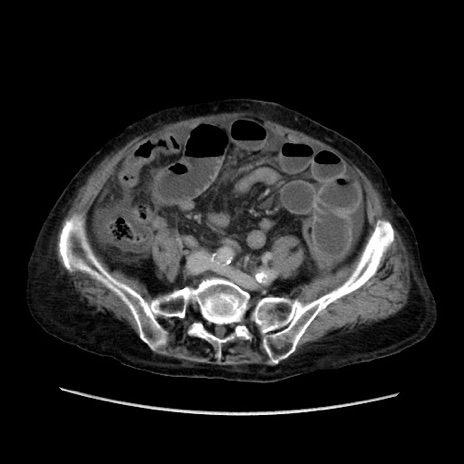

症例31(横断像)

【症例】80歳代 女性

【主訴】腹部膨満感

【現病歴】他院にて肝硬変にてフォロー中。1週間前から便秘、腹部膨満感、臍部腫瘤あり受診となる。

【既往歴】肝硬変

【身体所見】腹部膨隆あり、皮膚変化なし、疼痛なし。

【データ】WBC 4600、CRP 0.25